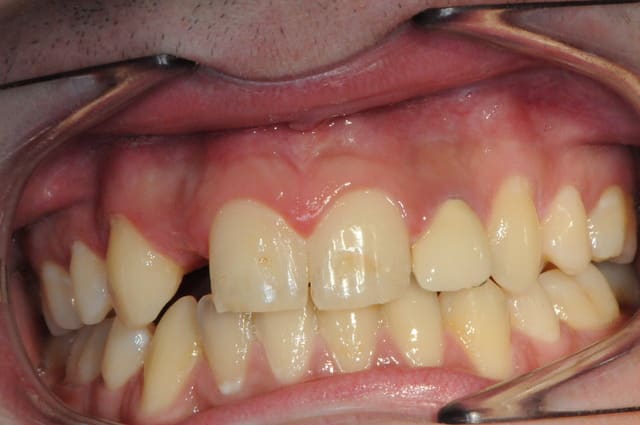

Ton cas est intéressant mais hormis la concavité vestibulaire, à mon avis largement rattrapable avec une expansion,

2 autres pièges attirent mon attention, c'est typique des agénésies des latérales.

1: Absence d'alignement des collets, à gérer impérativement en cours de chirurgie, sinon dent trop courte et inesthétique.

2: espace MD trop étroit à vue d'oeil, attention au type d'implant.

Si le col implantaire est trop large (sup à 3 mm de diam ) tu aura une compression gingivale et disparition des papilles.

Cordialement